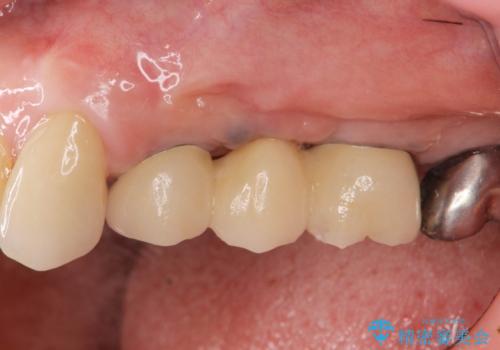

複数の奥歯の欠損 インプラントによる咬合機能回復

- 105.6万円(インプラント×2・チタンカスタムアバットメント×2・ジルコニアクラウン×3・仮歯×3)費用は治療当時の料金となります

しっかりと咬合機能の回復がなされ、また食事を楽しんでいただけるようになりました。